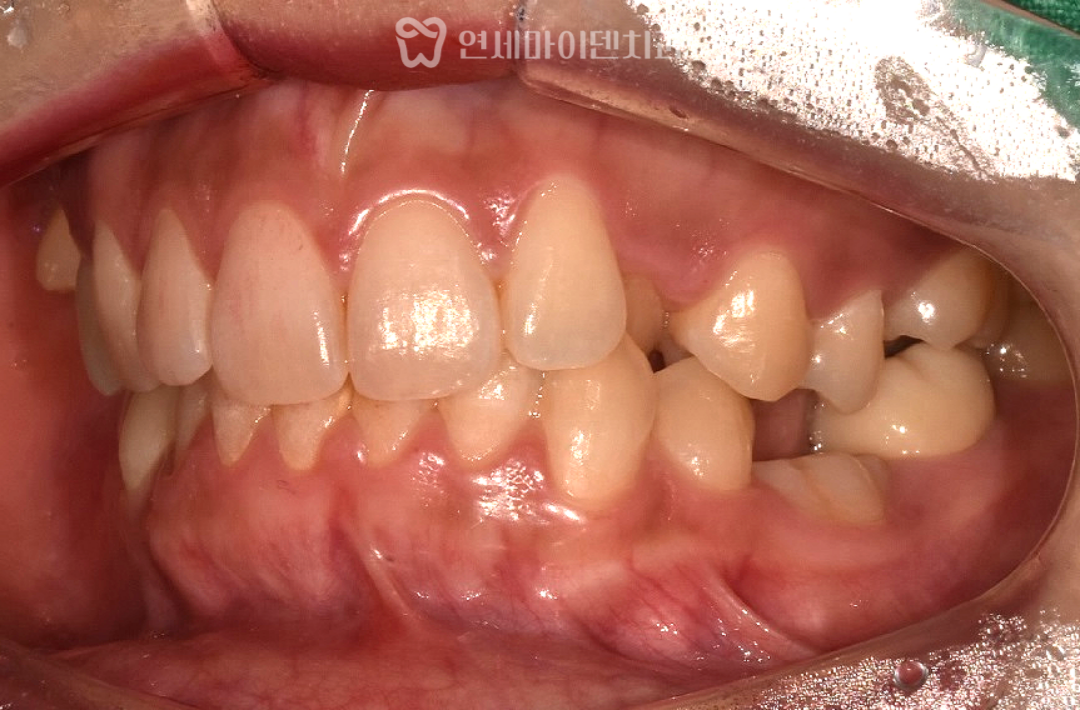

치료를 시작하면서 먼저 위아래 치아에

교정용 브라켓을 부착하고 치아 배열을 맞추기 시작했습니다.

특히 안쪽으로 들어간 송곳니가 배열될 수 있도록

공간을 확장하는 과정이 필요했습니다.

또한, 오른쪽 위 튀어나온 어금니는

미니스크류(미니 임플란트)를 이용해 제 위치로 당겨주었습니다.

교정 중에는 치아가 서로 부딪칠 수도 있어서,

아래쪽 치아에 임시로 파란 레진을 붙여서

교합을 띄우는 조치도 함께 진행했어요.

유치가 있던 부위는 발치 후 골 이식을 진행했고

교정치료 기간동안 공간을 확보한 뒤

임플란트를 식립하기로 했습니다.